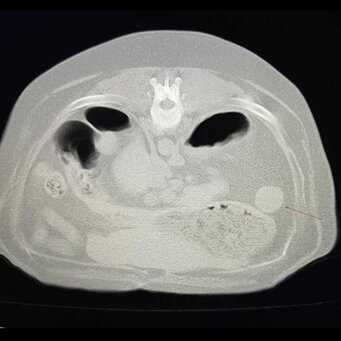

TAC VETERINARIA

La tomografia computerizzata (TAC) è un’indagine diagnostica, già molto in uso in medicina umana, che nell’ultimo decennio sta dimostrandosi ormai utile e a volte indispensabile anche nei nostri animali per approfondire lo studio di diverse patologie (ortopediche, neoplastiche, traumatologiche, neurologiche…).

La Clinica Veterinaria San Rocco ha pertanto recentemente introdotto un’apparecchiatura TAC multistrato, in grado di eseguire esami TC total body o di alcuni settori, senza e con mezzo di contrasto, in qualsiasi momento se ne palesi la necessità, sia in cane e gatto che in animali non convenzionali, collocandola in un reparto nuovo (Imaging VetSanRocco) contiguo ai locali della Clinica con accesso riservato esclusivamente ai pazienti destinati a questo tipo di indagine.

Il tempo richiesto per l’esecuzione delle scansioni è molto breve (qualche decina di secondi), per cui la procedura consente di minimizzare sia la durata dell’anestesia che l’esposizione alle radiazioni.